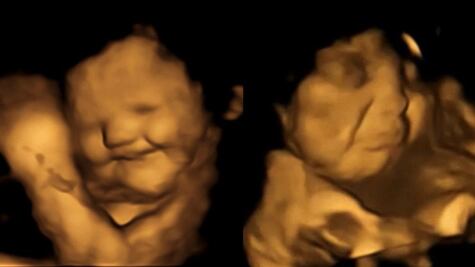

Esta investigación confirmó estudios anteriores que sugieren que los fetos pueden sentir gustos durante la gestación